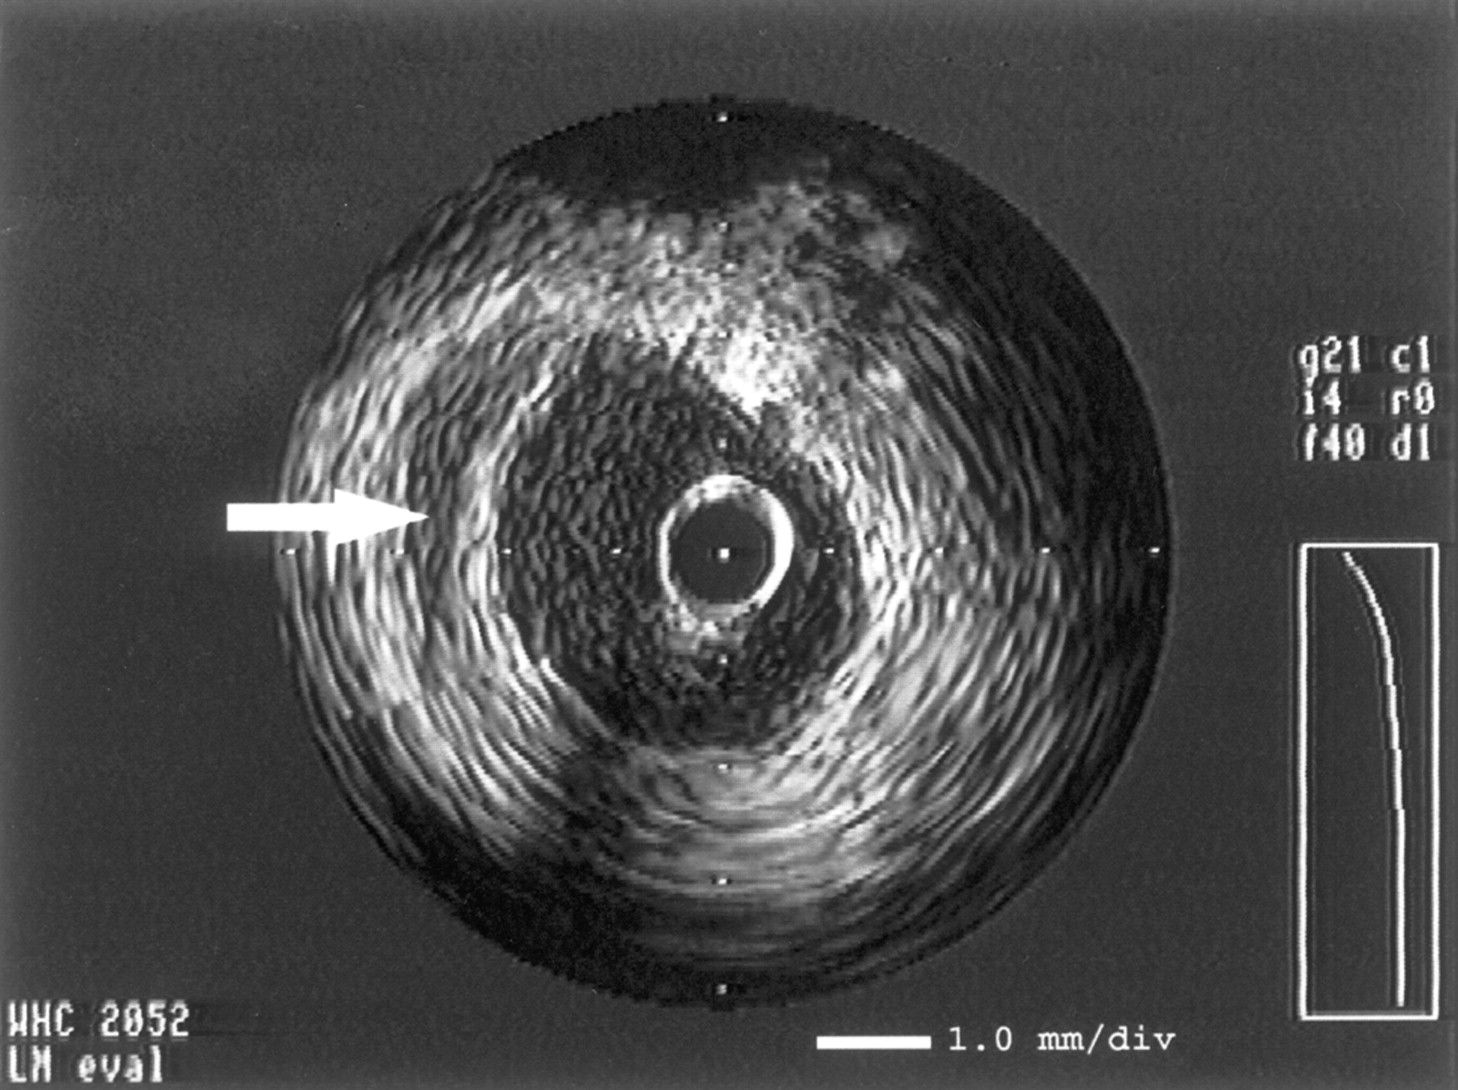

This IVUS cross-section shows:

Answer

• Full stent apposition

• Sub-stent hematoma

• Incomplete stent apposition

• Calcium